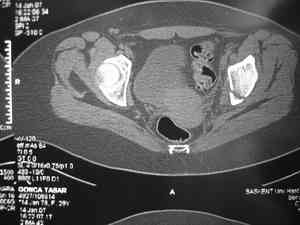

Спасибо за клинические примеры и комментарии. Если честно то просто восхищен представлеными R-ммами (классно сделали!!!). По поводу обсуждаемого больного: конечно КТ и дополнительные R-ммы сделаем. Но хочу напомнить, что после травмы прошло более 6 лет, на сегодняшний день клинически еще и R-ки признаки нестабильности эндопротеза( как бедренного компонента так и чашки). Хочется определиться как делать в аппарате или одномоментно открыто. Лично я склоняюсь к аппаратному лечению на первом этапе.

прилагаю пример с такой же давностью травмы, репонировали аппаратом